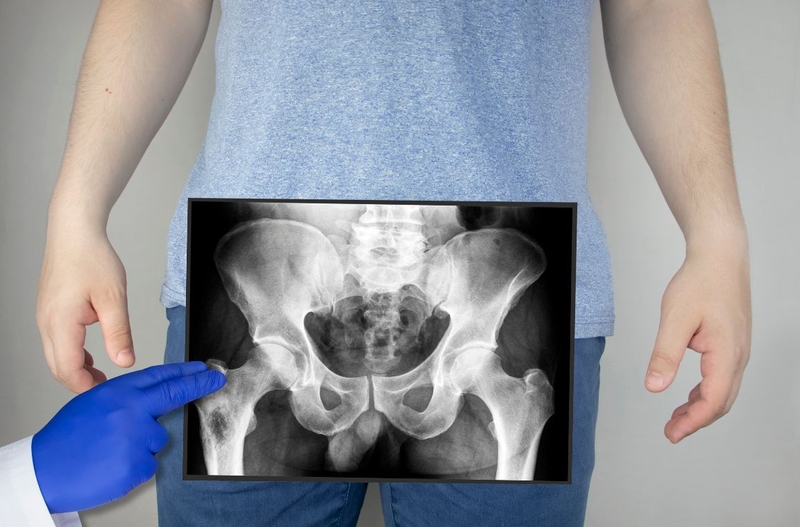

Chụp X quang khung chậu được chỉ định để chẩn đoán các bất thường, tổn thương hoặc bệnh lý ở khung chậu. Đặc biệt, đây cũng là xét nghiệm hình ảnh quan trọng giúp dự đoán khả năng sinh thường ở nữ giới.

Chụp X quang khung chậu là kỹ thuật chẩn đoán hình ảnh vùng xương chậu bằng máy chụp X quang và tia X. Kỹ thuật nhằm phát hiện, đánh giá, chẩn đoán các tổn thương, bất thường, bệnh lý ở vùng xương chậu. Thông qua chụp X quang vùng xương chậu, bác sĩ cũng đánh giá được khả năng sinh thường ở phụ nữ. Vậy kỹ thuật chụp X quang này có ý nghĩa gì và quy trình thực hiện cụ thể ra sao?

Chụp X quang là kỹ thuật dùng tia X chiếu vào khung xương chậu để thu được hình ảnh khung chậu - cấu trúc mà chúng ta không có khả năng quan sát bằng mắt thường. Kỹ thuật này đặc biệt có giá trị trong thăm khám, đánh giá, chẩn đoán các vấn đề hoặc bệnh lý liên quan đến khung xương chậu. Chụp X quang khung chậu diễn ra nhanh chóng, đơn giản, an toàn, không xâm lấn nhưng lại cho kết quả khá chính xác.